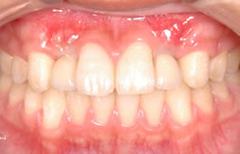

先欠(生まれつき歯がない)状態を矯正治療とインプラントで治療した症例

矯正で歯列を整え、先欠部にインプラントを埋入しセラミックの歯を入れて仕上げたケース。

約20年経過後も問題はございません。